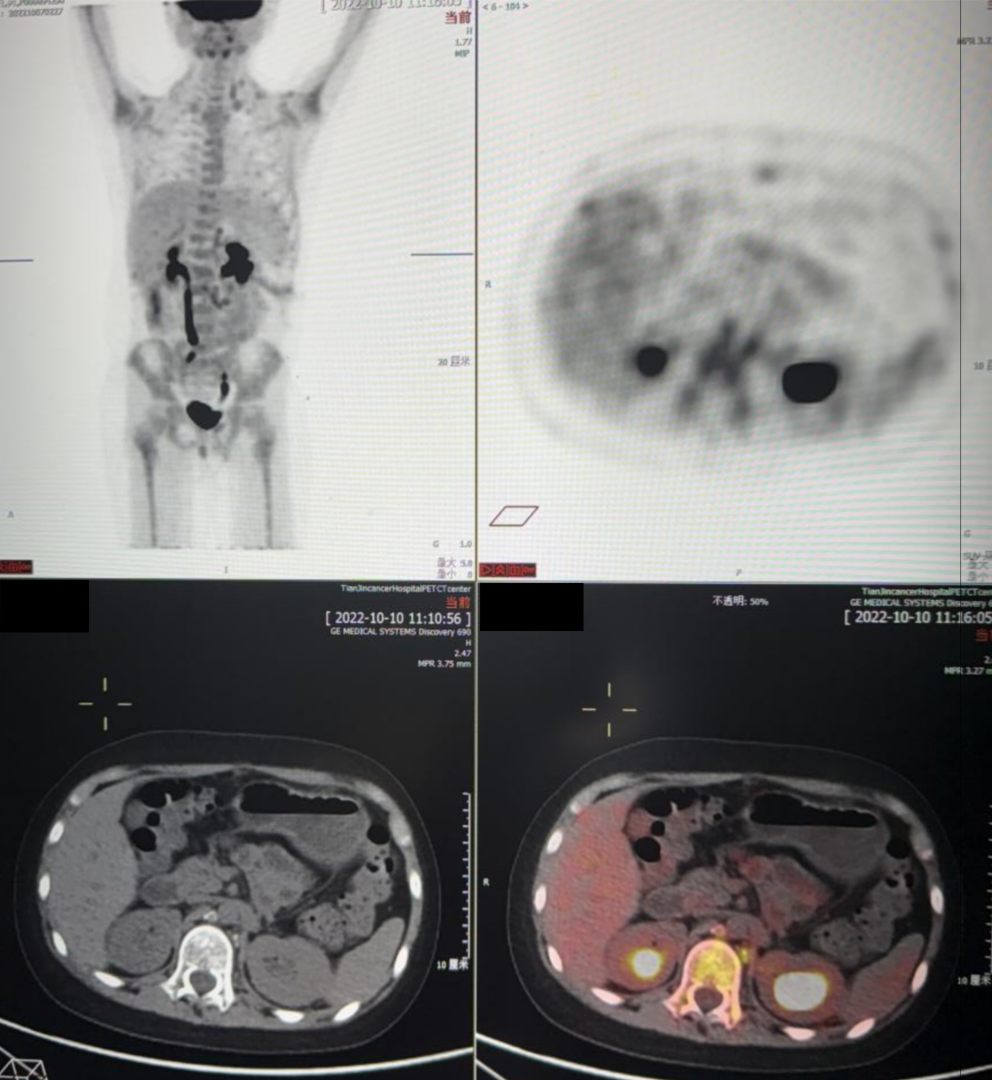

PET-CT(2022.5.19)

1. 左侧中下腹左肾旁不规则巨大肿物,PET显示异常放射性浓聚,考虑为恶性,神经母细胞瘤可能性大。

2. 左侧中下颈、锁区,后纵隔食管周围,坐下后胸膜下、双侧膈脚后、腹膜后腹主动脉及下腔静脉周围、双侧髂总血管周围、髂脉区多发结节及肿物,PET显示异常放射性浓聚,考虑为淋巴结转移。

3. 所见全身多发骨骼骨质密度不均及骨质破坏,PET显示异常放射性浓聚,考虑为转移。

移植前评估PET-CT(2022.10.10):

1. 左腹壁手术瘢痕,考虑为术后改变;

2. 左侧中下颈、锁区,后纵隔食管周围,左下后胸膜下、双侧膈脚后、腹膜后腹主动脉及下腔静脉周围、肠系膜间、双侧髂总血管周围、髂脉区多发结节及肿物较前明显减小、减少,部分消失,此次PET显示放射性浓聚程度较前减低,提示病灶代谢较前减低,部分仍存活性;

3. 所见全身多发骨质密度不均伴第11胸椎压缩变扁,总体示病情较前好转。